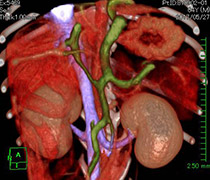

また、動物医療の高度化に伴い、外科手術の必要性は高くなっています。

当院では、腫瘍外科、整形外科、神経外科、軟部外科、眼科など様々な外科手術に対応しています。

さらに高度な検査、治療が必要な場合は、大学病院や専門の獣医師をご紹介いたします。